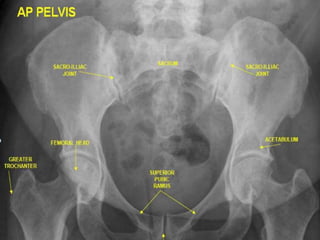

Reading the Abdominal Plain Film.

• Also known as the

“KUB” (kidney, ureter, &

bladder).

•Use a systematic

approach to

Interpretation.

– Lung bases & diaphragms.

– Bones.

– Soft tissues.

• Abnormal calcifications.

• Organs.